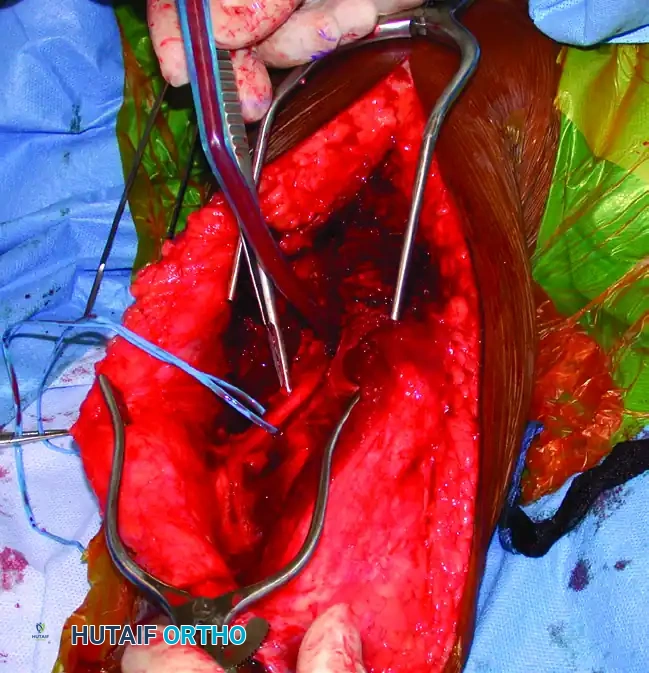

Identification and Mobilization of the Radial Nerve

The most critical step in the posterior approach is the safe identification and mobilization of the radial nerve. Iatrogenic radial nerve palsy is a devastating complication that must be avoided through systematic anatomic dissection.

- The Roadmap: Identify the lower lateral brachial cutaneous nerve within the subcutaneous tissue or superficial fascia. Follow this nerve proximally; it reliably leads directly to the radial nerve as it pierces the lateral intermuscular septum from the posterior to the anterior compartment.

- This intersection typically occurs at the level of the tourniquet. Once the radial nerve is definitively identified, release the tourniquet to minimize ischemic neuropraxia and allow for accurate assessment of hemostasis.

💎 Clinical Pearl: Radial Nerve Mobilization

Do not merely identify the radial nerve; mobilize it extensively. Free the nerve proximally, distally, anteriorly, and posteriorly. Incise the lateral intermuscular septum for at least 3 cm to prevent kinking or tethering of the nerve during fracture reduction and plate application.

- With the radial nerve protected (often using a vessel loop, though care must be taken not to apply excessive traction), incise the triceps off the periosteum to expose the humeral shaft.